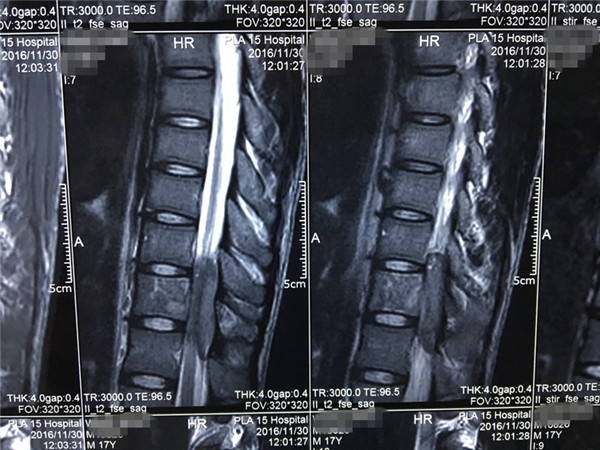

术前MRI

术前 MRI